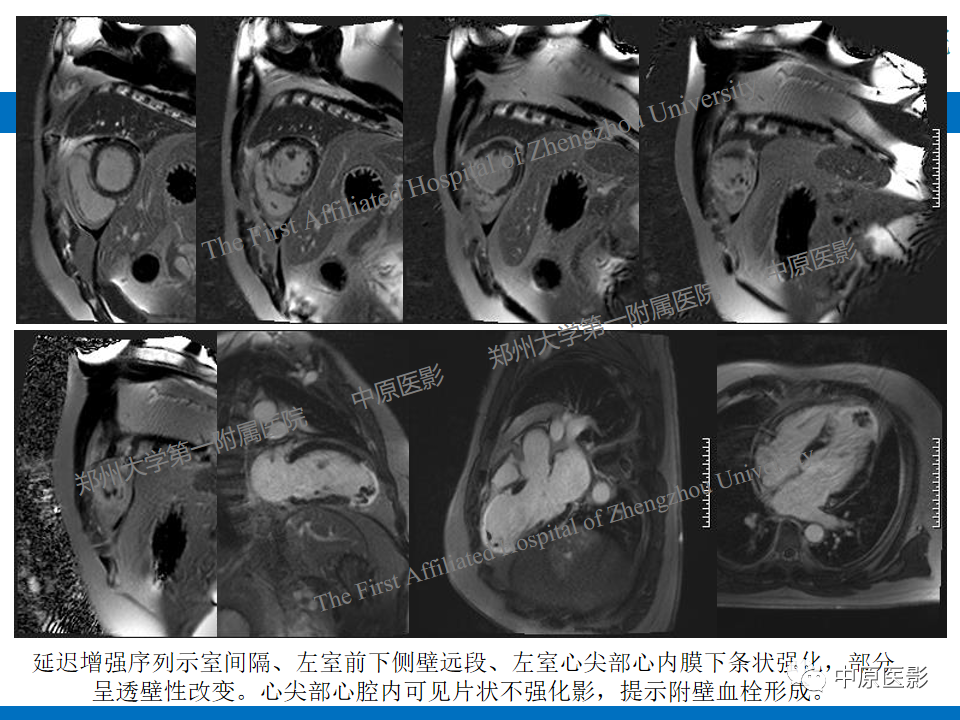

【病例】致心律失常性右室心肌病1例MR影像-2